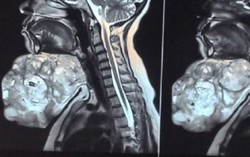

Bé 3 tháng tuổi mang bướu khổng lồ sau gáy mỏi mòn chờ phẫu thuật

Chính trị - Xã hội 15:33 31/01/2018Bé Zareena Mangro ra đời tại tỉnh Balochistan (Pakistan) với chứng thoát vị não, đang phải mòn mỏi chờ đợi để được phẫu thuật.